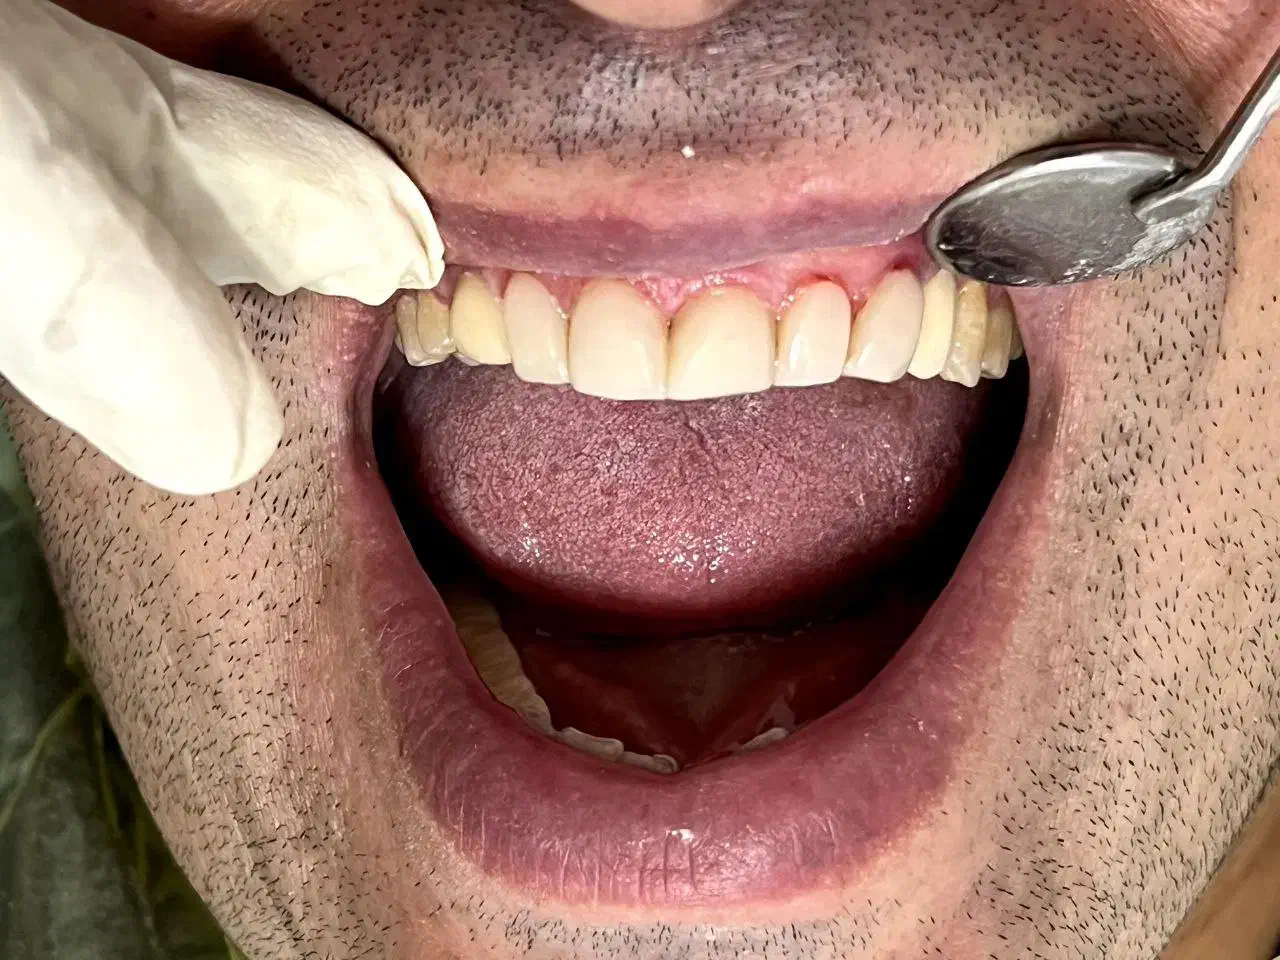

خدمات دندان پزشکی با متناسب شرایط و بودجه شما

ساعت فعالیت ۹صبح الی ۲۴ حتی روز های تعطیل و جمعه دندان پزشکی بزرگسال و اطفال با شش سال سابقه ی کاری طرف قرارداد با بیمه ی تکمیلی ( تامین اجتماعی البرز کوثر رازی ایران و معلم و دانا و آتیه سازان حافظ بانک کشاورزی و sos ) تعرفه برای مراجعین بدون بیمه تکمیلی جرم گیری ۹۰۰هزار تومان الی یک میلیون و دویست کشیدن ساده ۴۰۰الی ۷۰۰هزار تومان کشیدن دندان عقل ۹۰۰هزار تومان جراحی دندان ۱۶۰۰الی۱۸۰۰ جراحی دندان عقل ۱۸۰۰ الی ۲ ترمیم ۱۵۰۰ الی ۱۷۰۰ کامپوزیت ونیر از ۱۵۰۰ عصب کشی و ترمیم دندان ۲۷۰۰الی۳۹۰۰ روکش های معمولی ۳۴۰۰ روکش های سرامیک ۴۳۰۰ ایمپلنت با روکش ۱۵الی ۱۷میلیون کلیه خدمات دندان پزشکی مخصوص اطفال (عصب کشی ترمیم کشیدن جرم گیری روکش) شرایط اقساطی با دریافت چک صیاد امکان پذیر میباشد ادرس رشت گاز دروازه لاکان مسجد امیرالمومنین کوچه ی ۱۶متری سمیه جهت نوبت دهی در دیوار خدماتی ک درخواست دارین رو به همراه شماره تماس ارسال بفرمایید همه روزه حتی روز های تعطیل